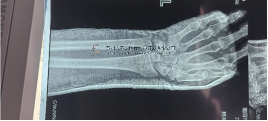

成教授重點(diǎn)介紹了其團(tuán)隊(duì)研發(fā)的六軸機(jī)器人輔助復(fù)位固定技術(shù)——《基于數(shù)字算法PILON骨折影像識(shí)別定位的機(jī)器人輔助復(fù)位固定技術(shù)研究》,以及《三臂機(jī)器人牽拉復(fù)位下肢骨折微創(chuàng)固定中的應(yīng)用初探》。在人工智能時(shí)代背景下,成教授團(tuán)隊(duì)將理念轉(zhuǎn)化為成熟技術(shù),實(shí)現(xiàn)了從理論到臨床應(yīng)用的重大突破。

馬不停蹄,人不歇腳。在南陽市中醫(yī)院獨(dú)山院區(qū)(國家中醫(yī)骨傷區(qū)域醫(yī)療中心)剛剛完成了首例兒童小腿骨折骨折六軸機(jī)器人復(fù)位彈力微創(chuàng)釘固定手術(shù)。2025年11月5日,又來到北京。參加中關(guān)村“火花”活動(dòng)——中國中醫(yī)科學(xué)院望京醫(yī)院2025年科技成果專場推介會(huì)。會(huì)議旨在加強(qiáng)中醫(yī)藥領(lǐng)域產(chǎn)學(xué)研協(xié)同創(chuàng)新,搭建科技成果轉(zhuǎn)化與資源對(duì)接平臺(tái),助力項(xiàng)目快速落地與產(chǎn)業(yè)化發(fā)展。

成永忠教授智能接骨團(tuán)隊(duì)研發(fā)的骨折手術(shù)機(jī)器人系統(tǒng),通過整合六軸定位、數(shù)字算法影像識(shí)別及多臂協(xié)同操作等關(guān)鍵技術(shù),實(shí)現(xiàn)了PILON骨折等四肢復(fù)雜骨折的精準(zhǔn)復(fù)位與微創(chuàng)固定。該系統(tǒng)在中西醫(yī)結(jié)合理念指導(dǎo)下,將CO接骨架與配套智能裝備解雇機(jī)器人技術(shù)相融合,標(biāo)志著骨科手術(shù)正在由傳統(tǒng)經(jīng)驗(yàn)?zāi)J较驍?shù)字化、智能化方向轉(zhuǎn)型。